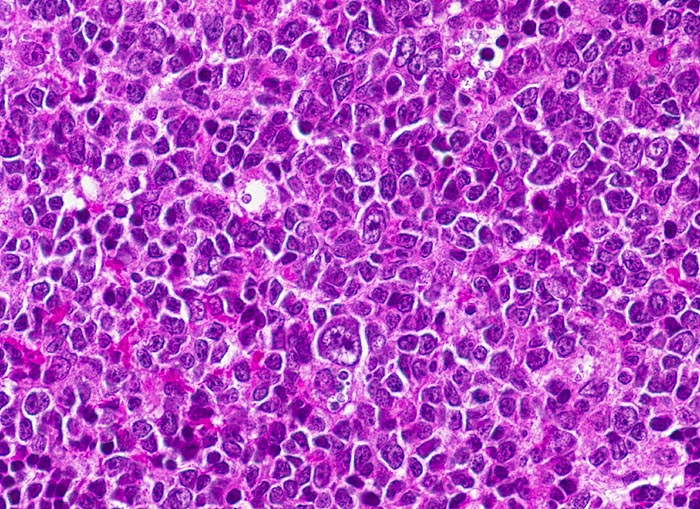

infektiöse Mononukleose

Entzündung infektiös

Tonsille

Lymphatische Gewebe, KM, Milz

Aktivierung der interfollikulären T-Zone (=sogenannte bunte Pulpahyperplasie mit Vermehrung verschiedener Zellarten). Beachte die hodgkinartigen Zellen (=reaktive/aktivierte B- resp. T-Lymphozyten).

Tonsillektomie bei einem Studenten mit Angina, Lymphknotenschwellungen und einer Lymphozytose im Blut.

Differentialdiagnose der Mononukleose: grosszelliges Non-Hodgkin Lymphom, Morbus Hodgkin (Reed-Sternberg-Zellen ähnliche Zellen können bei Mononukleose vorkommen!), andere Erreger (Röteln, Toxoplasmose), reaktive Hyperplasie bei Medikamenten-Allergie oder Autoimmunität.

Diagnosebestätigung durch immunhistologischen Nachweis des Latent Membrane Antigens (LMA) im Zytoplasma der infizierten Zellen und/oder des Epstein-Barr Virus nukleären Antigens (EBNA) in EBV-transformierten Immunoblasten oder molekularbiologischer in-situ Nachweis von EBV-DNA (EBER-1). Virusserologie.

Histologie

400